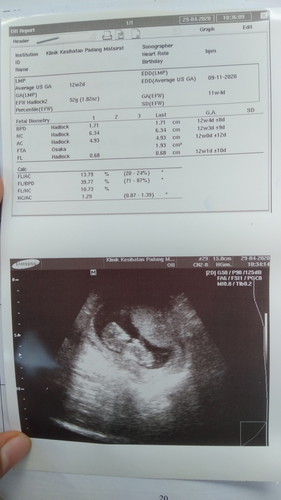

Salam nak tanya. Masa first scan dulu due 23.11.2020. (scan dekat klinik swasta) pastu bila buat buku pink p klinik desa nurse tulis due kat buku pink 19.11.2020. lepastu harini pula kena pergi klinik kesihatan jumpa doktor dan scan. Dan doktor pula bgitau dia dapat due 9.11.2020. pastu lagi 2 minggu doktor suruh pergi scan lagi untuk kepastian due. Ada tak yang pengalaman macamni? Gambar tu gambar scan yang Hari ni.